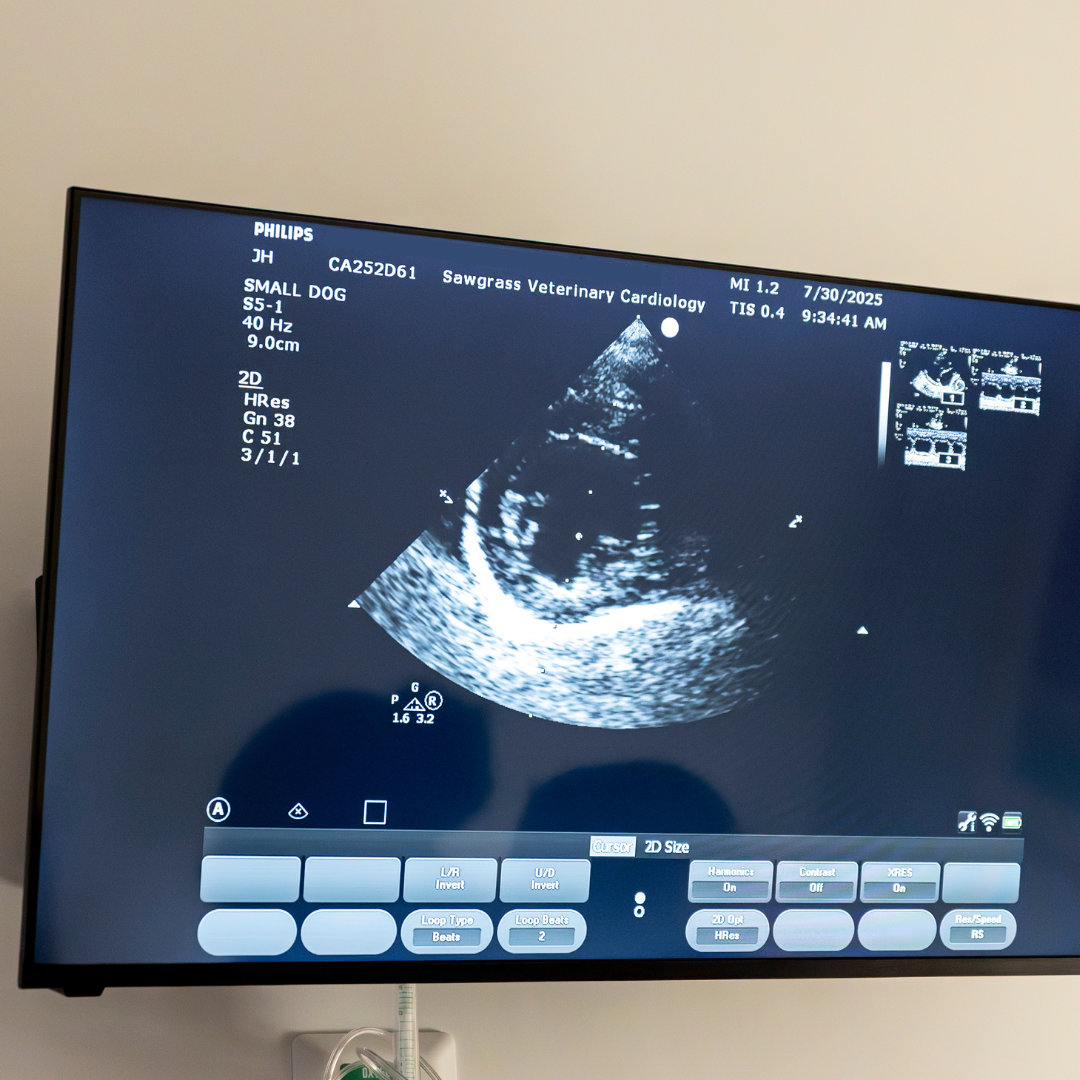

Echocardiography

An echocardiogram is a non-invasive ultrasound of the heart that allows us to see the heart beating in real time. It provides detailed information about heart chamber size, valve function, muscle thickness, and blood flow patterns—all critical for diagnosing conditions like valve disease, cardiomyopathy, congenital defects, or fluid around the heart. Unlike an X-ray, which gives a static image, an echocardiogram shows how the heart functions moment to moment, allowing for more accurate assessment and treatment planning.

At Sawgrass Veterinary Cardiology, we perform all echocardiograms with the pet owner present in the room, so you can be part of the process and see what we see. Most pets do not need sedation and are gently positioned on a padded table while we scan their chest with a specialized probe. The test is painless, typically takes about 10-15 minutes, and results are discussed with you in real time so you leave with a clear understanding of your pet’s heart health and any next steps.